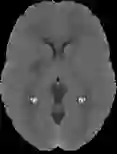

Accurate infarct segmentation in non-contrast CT (NCCT) images is a crucial step toward computer-aided acute ischemic stroke (AIS) assessment. In clinical practice, bilateral symmetric comparison of brain hemispheres is usually used to locate pathological abnormalities. Recent research has explored asymmetries to assist with AIS segmentation. However, most previous symmetry-based work mixed different types of asymmetries when evaluating their contribution to AIS. In this paper, we propose a novel Asymmetry Disentanglement Network (ADN) to automatically separate pathological asymmetries and intrinsic anatomical asymmetries in NCCTs for more effective and interpretable AIS segmentation. ADN first performs asymmetry disentanglement based on input NCCTs, which produces different types of 3D asymmetry maps. Then a synthetic, intrinsic-asymmetry-compensated and pathology-asymmetry-salient NCCT volume is generated and later used as input to a segmentation network. The training of ADN incorporates domain knowledge and adopts a tissue-type aware regularization loss function to encourage clinically-meaningful pathological asymmetry extraction. Coupled with an unsupervised 3D transformation network, ADN achieves state-of-the-art AIS segmentation performance on a public NCCT dataset. In addition to the superior performance, we believe the learned clinically-interpretable asymmetry maps can also provide insights towards a better understanding of AIS assessment. Our code is available at https://github.com/nihaomiao/MICCAI22_ADN.